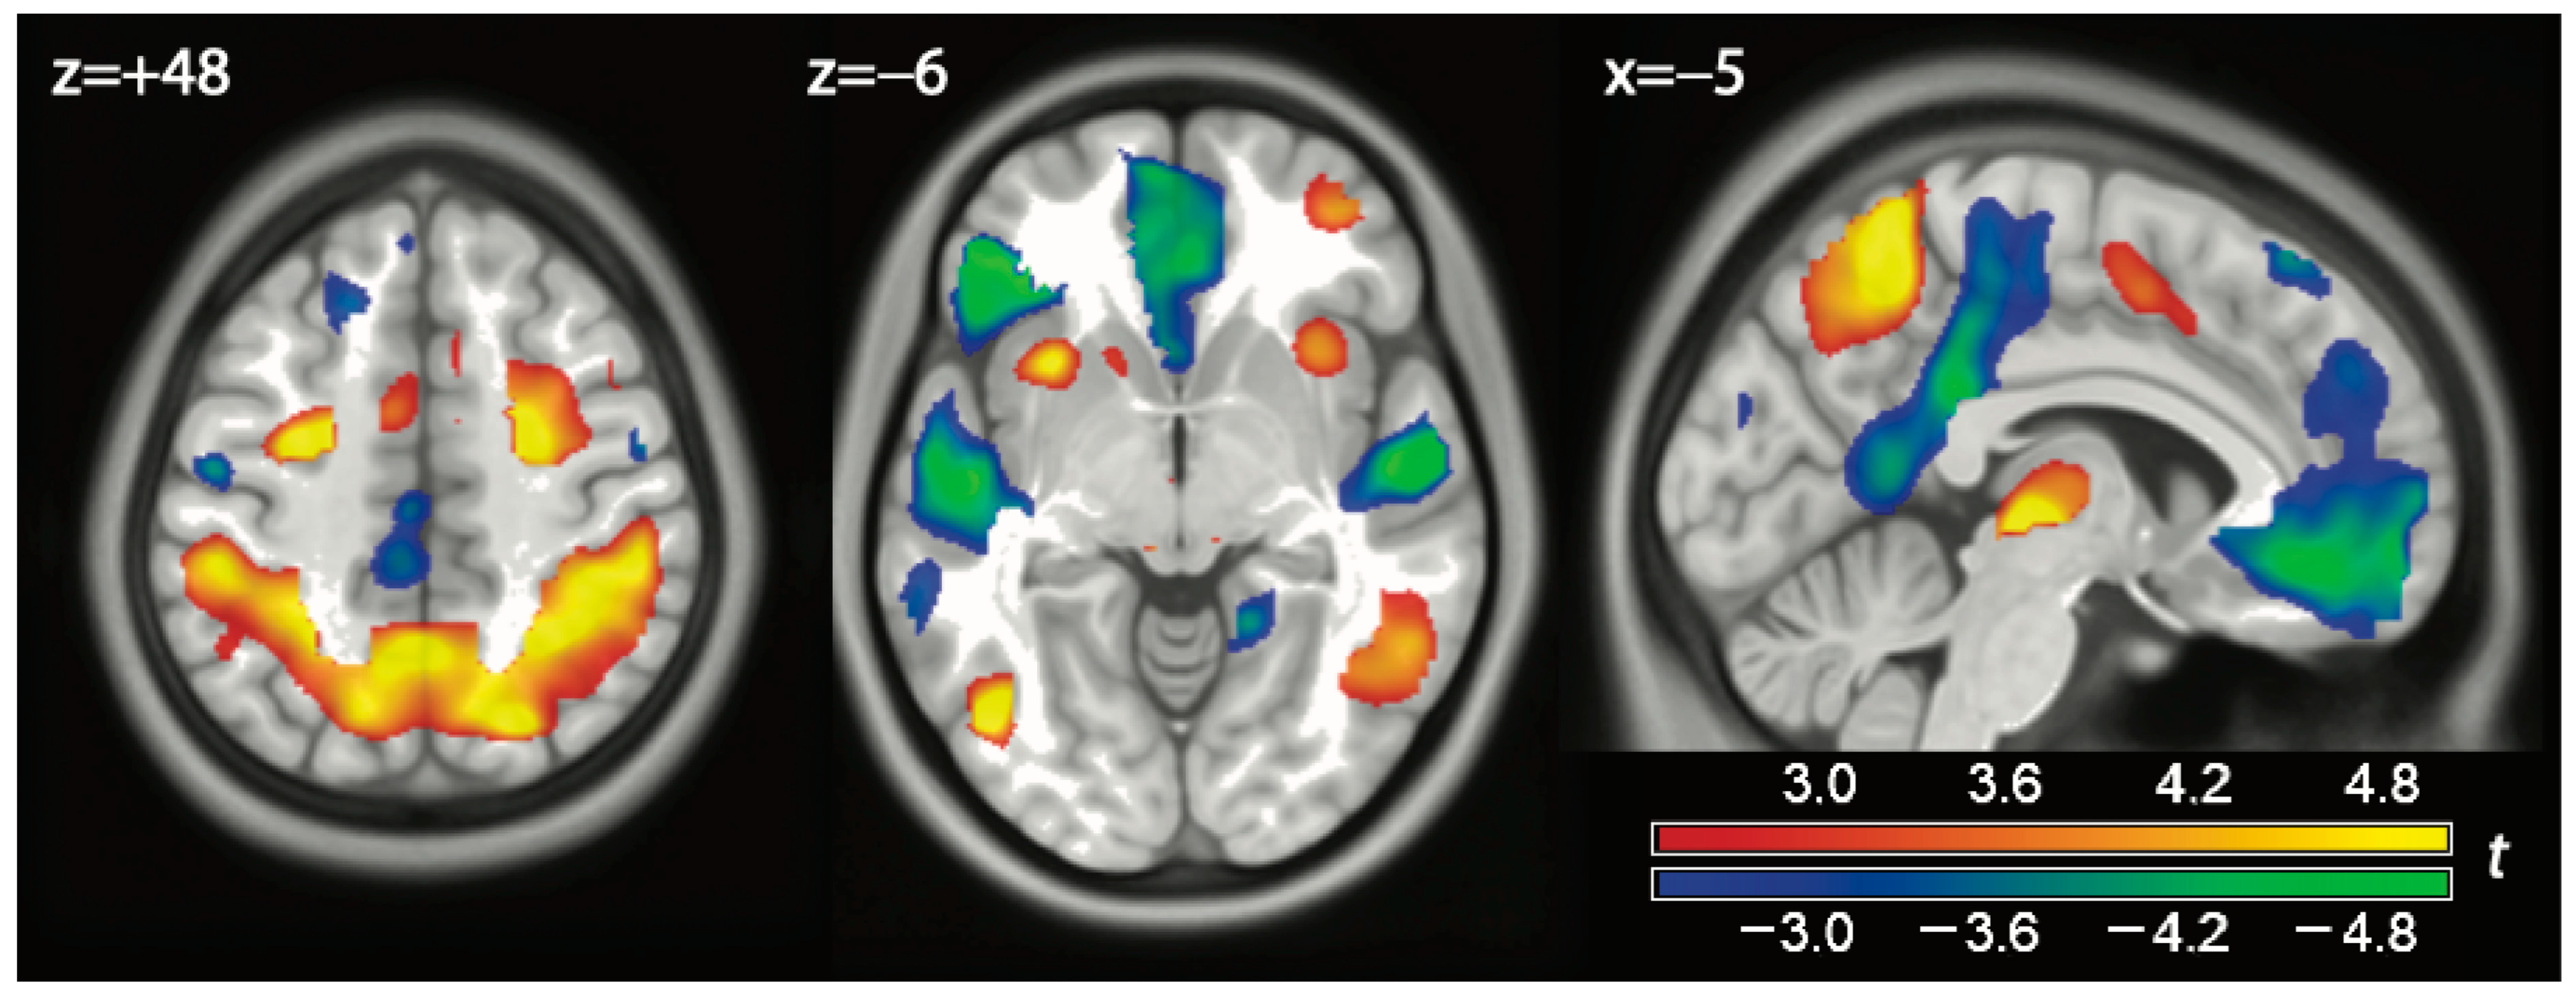

| Play vs. (watch or exclusion) | |||||||

| 1 | Left Middle Temporal Gyrus (BA 37) | −46 −68 0 | 8.416 | <0.0001 | 0.000 | 581 | 0.013 |

| Left Culmen (BA 37) | −42 −50 −26 | 5.965 | <0.0001 | 0.015 | |||

| 2 | Left Middle Frontal Gyrus (BA 6) | −28 −6 48 | 7.878 | <0.0001 | 0.000 | 535 | 0.015 |

| Left Middle Frontal Gyrus (BA 6) | −26 −8 62 | 7.068 | <0.0001 | 0.001 | |||

| 3 | Left Inferior Parietal Lobule (BA 40) | −48 −36 32 | 7.838 | <0.0001 | 0.000 | 6504 | <0.001 |

| Left Superior Parietal Lobule (BA 7) | −14 −68 58 | 6.854 | <0.0001 | 0.003 | |||

| Left Precuneus (BA 7) | −2 −52 54 | 6.841 | <0.0001 | 0.003 | |||

| Left Precuneus (BA 7) | −6 −54 64 | 6.767 | <0.0001 | 0.004 | |||

| Left Precuneus (BA 7) | −8 −56 54 | 6.479 | <0.0001 | 0.005 | |||

| Right Precuneus (BA 7) | 22 −72 48 | 6.364 | <0.0001 | 0.007 | |||

| Right Superior Parietal (BA 7) | 14 −68 60 | 6.065 | <0.0001 | 0.013 | |||

| Left Superior Parietal (BA 7) | −28 −50 68 | 6.058 | <0.0001 | 0.013 | |||

| Right Postcentral Gyrus (BA 2) | 48 −34 54 | 5.728 | <0.0001 | 0.024 | |||

| Left Inferior Parietal Lobule (BA 40) | −32 −44 40 | 5.728 | <0.0001 | 0.024 | |||

| Right Inferior Parietal Lobule (BA 40) | 52 −36 40 | 5.655 | <0.0001 | 0.027 | |||

| Right Superior Parietal Lobule (BA 7) | 34 −50 60 | 5.620 | <0.0001 | 0.029 | |||

| Right Inferior Parietal Lobule (BA 40) | 38 −46 42 | 5.414 | <0.0001 | 0.043 | |||

| Right Precuneus (BA 7) | 14 −56 54 | 5.383 | <0.0001 | 0.044 | |||

| Right Inferior Parietal Lobule (BA 40) | 40 −38 48 | 5.367 | <0.0001 | 0.045 | |||

| Left Precuneus (BA 7) | −26 −52 44 | 5.284 | <0.0001 | 0.054 | |||

| Right Sub-Gyral (BA 40) | 40 −38 38 | 5.167 | <0.0001 | 0.068 | |||

| Right Precuneus (BA 7) | 20 −62 40 | 5.022 | <0.0001 | 0.091 | |||

| Left Inferior Parietal Lobule (BA 40) | −38 −44 58 | 4.269 | 0.0001 | 0.332 | |||

| 4 | Left Posterior Thalamus | −6 −22 −2 | 7.201 | <0.0001 | 0.001 | 250 | 0.050 |

| Right Posterior Thalamus | 6 −22 −2 | 5.632 | <0.0001 | 0.028 | |||

| 5 | Right Superior Frontal Gyrus (BA 6) | 18 12 62 | 6.352 | <0.0001 | 0.007 | 1117 | 0.003 |

| Right Temporal Pole (BA 20) | 22 −4 50 | 6.314 | <0.0001 | 0.008 | |||

| Right Middle Frontal Gyrus (BA 6) | 30 −6 60 | 6.214 | <0.0001 | 0.010 | |||

| Right Middle Frontal Gyrus (BA 6) | 30 12 60 | 5.726 | <0.0001 | 0.024 | |||

| 6 | Right Inf Temporal Gyrus (BA 37) | 48 −52 −26 | 6.276 | <0.0001 | 0.009 | 1046 | 0.004 |

| Right Inf Temporal Gyrus (BA 37) | 60 −54 −14 | 5.132 | <0.0001 | 0.072 | |||

| Right Middle Temporal Gyrus (BA 21) | 52 −50 2 | 5.077 | <0.0001 | 0.081 | |||

| Right Inf Temporal Gyrus (BA 37) | 56 −58 −22 | 5.020 | <0.0001 | 0.091 | |||

| Right Fusiform Gyrus (BA 37) | 38 −48 −24 | 4.653 | <0.0001 | 0.178 | |||

| Right Inf Temporal Gyrus (BA 37) | 44 −46 −12 | 4.117 | 0.0002 | 0.412 | |||

| Right Sup Temporal Gyrus (BA 22) | 60 −46 16 | 4.080 | 0.0002 | 0.431 | |||

| Right Inf Temporal Gyrus (BA 37) | 48 −58 −4 | 4.026 | 0.0002 | 0.461 | |||

| 7 | Left Insula | −30 14 −4 | 5.496 | <0.0001 | 0.036 | 176 | 0.077 |

| (Watch or exclusion) vs. play | |||||||

| 8 | Right Sup Temporal Gyrus (BA 21) | 60 −10 −2 | −7.350 | <0.0001 | 0.001 | 1593 | 0.001 |

| Right Insula | 42 −16 4 | −5.886 | <0.0001 | 0.016 | |||

| Right Insula | 38 −14 20 | −4.981 | <0.0001 | 0.098 | |||

| Right Postcentral Gyrus (BA 43) | 62 −6 18 | −4.795 | <0.0001 | 0.139 | |||

| Right Lentiform Nucleus (Putamen) | 30 −10 6 | −3.768 | 0.0005 | 0.600 | |||

| 9 | Left Middle Frontal Gyrus (BA 47) | −48 40 −6 | −7.226 | <0.0001 | 0.001 | 1360 | 0.001 |

| Left Inferior Frontal Gyrus (BA 47) | −38 32 −2 | −5.684 | <0.0001 | 0.024 | |||

| Left Middle Temporal Gyrus (BA 21) | −50 10 −30 | −5.547 | <0.0001 | 0.032 | |||

| Left Inferior Frontal Gyrus (BA 47) | −48 28 −4 | −5.145 | <0.0001 | 0.071 | |||

| Left Inferior Frontal Gyrus (BA 47) | −50 28 12 | −4.917 | <0.0001 | 0.111 | |||

| Left Temporal Pole (BA 20) | −38 0 −46 | −4.613 | <0.0001 | 0.193 | |||

| Left Temporal Pole (BA 38) | −44 24 −18 | −4.118 | 0.0002 | 0.403 | |||

| 10 | Left Superior Temporal Gyrus (BA 22) | −48 −14 0 | −6.037 | <0.0001 | 0.011 | 1891 | 0.001 |

| Left Superior Temporal Gyrus (BA 22) | −60 −6 10 | −5.471 | <0.0001 | 0.037 | |||

| Left Superior Temporal Gyrus (BA 21) | −58 −10 −2 | −5.382 | <0.0001 | 0.044 | |||

| Left Insula | −40 −20 8 | −5.280 | <0.0001 | 0.055 | |||

| Left Precentral Gyrus (BA 4/6) | −50 −12 44 | −4.429 | <0.0001 | 0.263 | |||

| Left Middle Temporal Gyrus (BA20) | −50 −16 −18 | −4.309 | 0.0001 | 0.313 | |||

| Left Precentral Gyrus (BA4) | −50 −12 28 | −4.280 | 0.0001 | 0.325 | |||

| Left Superior Temporal Gyrus (BA 22) | −60 −30 4 | −3.724 | 0.0005 | 0.628 | |||

| Left Superior Temporal Gyrus (BA 22) | −62 −40 4 | −3.703 | 0.0006 | 0.639 | |||

| 11 | Ventral Anterior Cingulum (BA 11) | 0 38 −12 | −5.559 | <0.0001 | 0.032 | 1320 | 0.001 |

| Ventral Anterior Cingulum (BA 11) | −8 58 −22 | −4.900 | <0.0001 | 0.114 | |||

| Left Medial Frontal Gyrus (BA 10) | −6 58 −8 | −4.788 | <0.0001 | 0.141 | |||

| Left Superior Frontal Gyrus (BA 10) | −12 64 2 | −4.272 | 0.0001 | 0.328 | |||

| Left Anterior Cingulate (BA 25) | −2 16 −6 | −3.894 | 0.0003 | 0.526 | |||